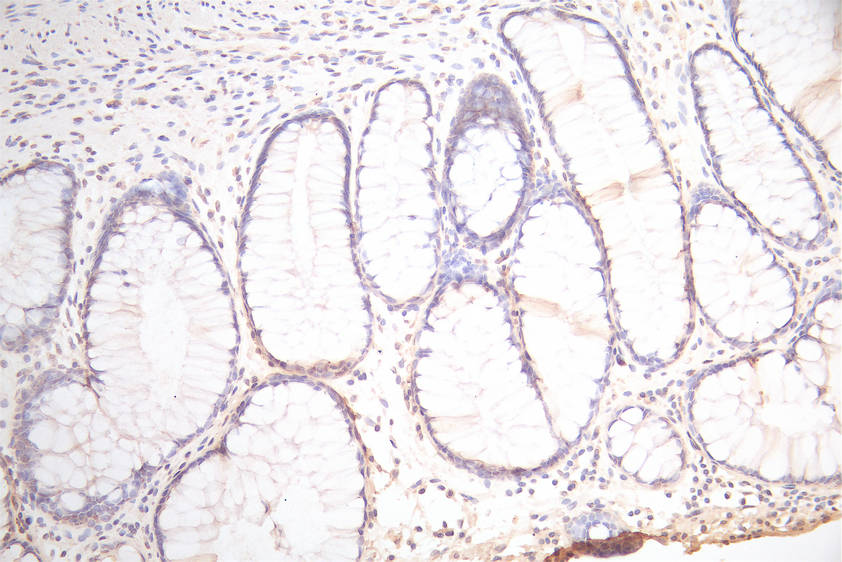

IHC image of CSB-RA017739MA1HU diluted at 1:300 and staining in paraffin-embedded human colorectal cancer performed on a Leica BondTM system. After dewaxing and hydration, antigen retrieval was mediated by high pressure in a citrate buffer (pH 6.0). Section was blocked with 10% normal goat serum 30min at RT. Then primary antibody (1% BSA) was incubated at 4°C overnight. The primary is detected by a Goat anti-Mouse IgG labeled by HRP and visualized using 0.05% DAB.